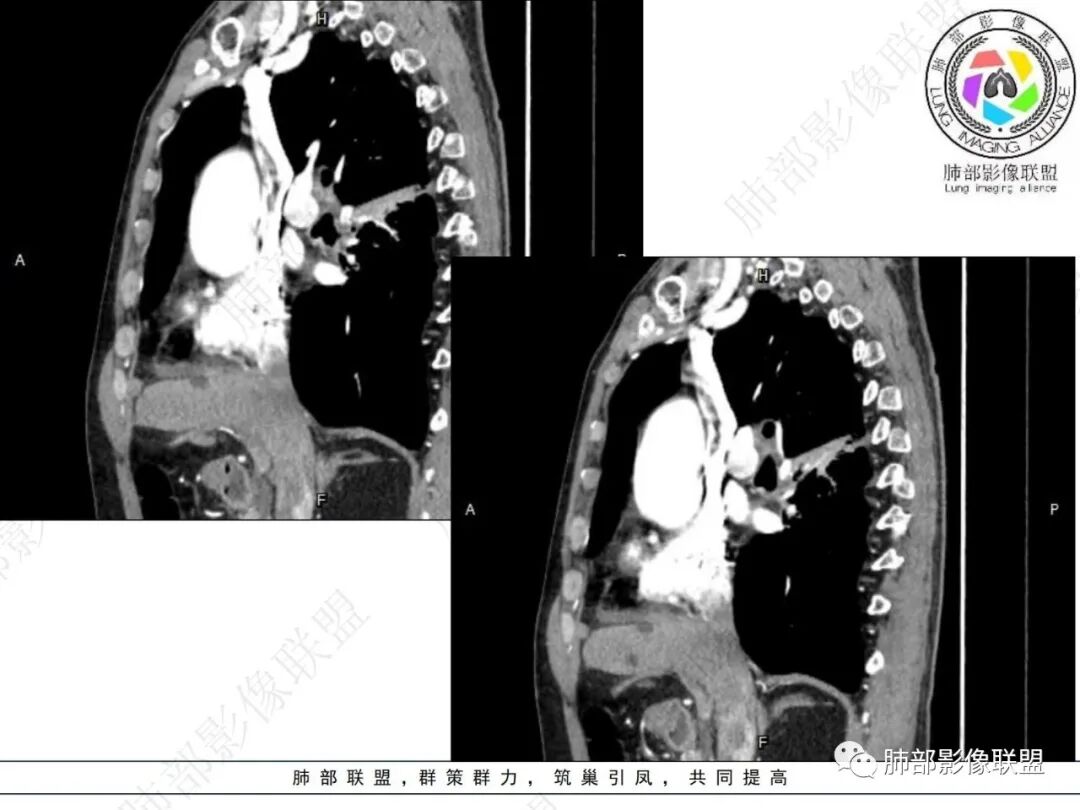

后纵隔,位于奇食窝右侧肿块,形态不规则,明显强化,右肺下叶背段支气管受压,并右肺下叶背段为主阻性炎症,右肺斜裂胸膜增厚,见多发微小串珠结节,纵隔内淋巴结肿大,与主体病灶强化性质相同,另外右下肺静脉主干边缘不规则(侵蚀破坏?),老年男性,2月前夜间刺激性干咳为主,方向恶性,纵隔旁型肺Ca,补充重建供血支气管动脉!

右肺下叶沿肺叶肺段分布斑片、条片状影,以下叶背段为显,边缘模糊,内可见支气管走行,局部支气管管壁增厚,右侧胸腔少量积液。纵隔隆突下可见不均匀软组织密度影,与周围结构分界不清,内见气体密度影,与食管及相邻右肺支气管之间未显示通道。邻近食管下段壁明显不规则增厚,增强后食管管壁明显不均匀强化,可见线样强化的连续完整粘膜影。

3.综合分析:

对比患者3月份的CT图,原隆突下存在增大钙化淋巴结,现在出现气体影,且钙化显示不清,应想到淋巴结结核破溃成瘘可能性。

这个病例提示我们纵隔内淋巴结伴钙化或肺内结核伴钙化,可能会因患者的免疫力下降使结核复燃。